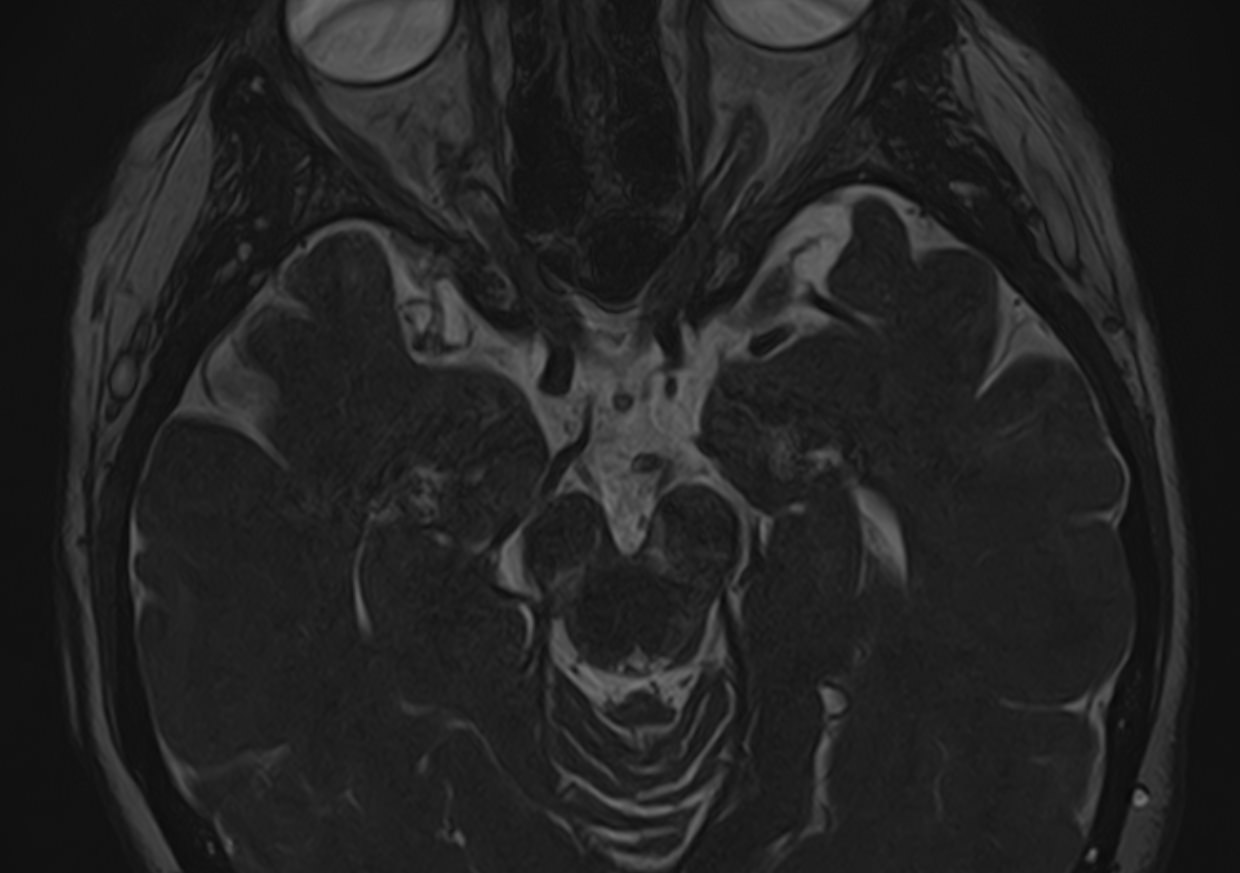

Магнитно-резонансная томография позволяет детально визуализировать изменения черепных нервов и прилегающих структур. В клинике «Доступная медицина» для точной диагностики причин поражения черепно-мозговых нервов применяется новейший высокопольный 32-канальный томограф TOSHIBA VANTAGE TITAN 1,5 Тесла, который обладает высокой чувствительностью и способностью определить минимальные изменения исследуемого органа.

Признаки нарушения функций ЧМН разнообразны. Причинами поражения могут быть серьезные заболевания, которые требуют незамедлительного обращения к врачу. Для установления точного диагноза в комплексе с другими методами используют МРТ и КТ головного мозга. Оба исследования имеют свои особенности. Компьютерная томография позволяет хорошо визуализировать изменения костной ткани. На МР-изображениях лучше просматриваются мягкотканные структуры, поэтому МРТ головного мозга с прицельным осмотром черепно-мозговых нервов является методом выбора в подобных случаях.